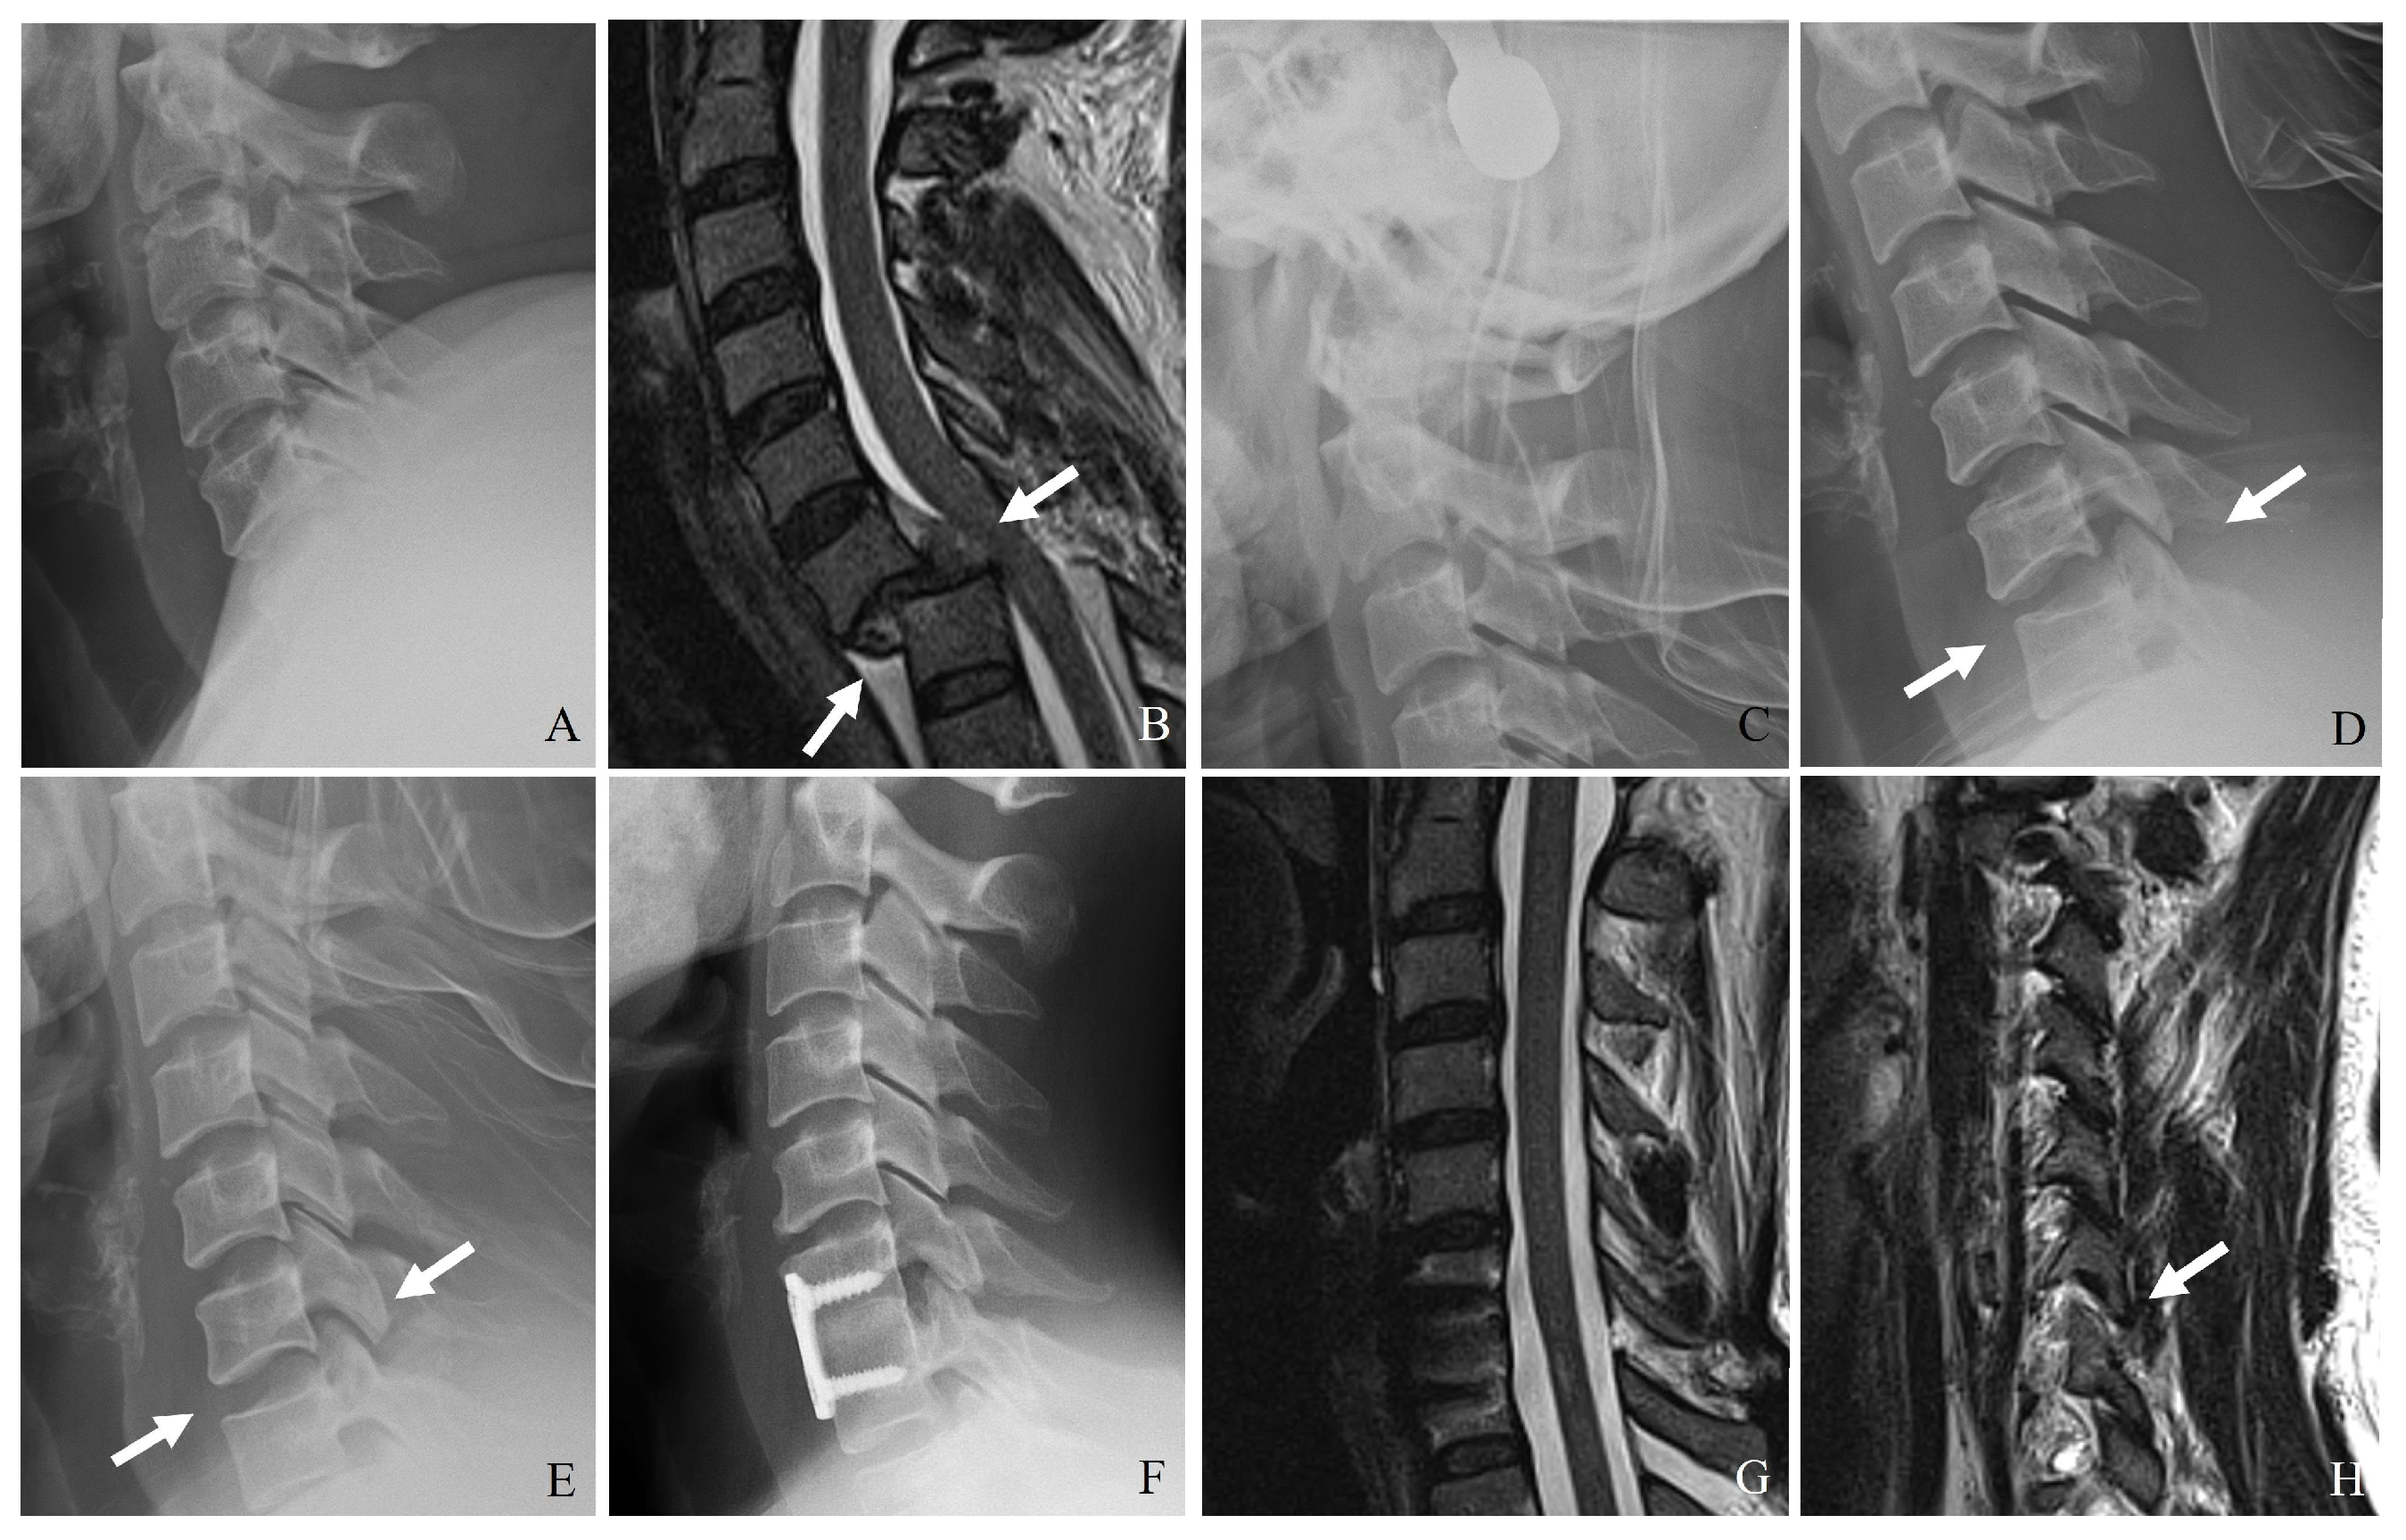

3.1. Plain Radiography

3.3. Magnetic Resonance Imaging (MRI)

| F1 Fracture | Nondisplaced or minimally displaced facet fracture | CT: Hairline or incomplete fracture without subluxation or misalignment. MRI: Minimal or no disruption of the DLC. | Mechanically stable; treated conservatively with immobilization. |

| F2 Fracture | Displaced facet fracture without significant instability | CT: Displaced fracture, but no complete subluxation or dislocation. Fracture extends < 40% into vertebral body. MRI: Partial PLC injury, intact DLC. | May be treated conservatively; surgical stabilization if symptoms progress. |

| F3 Fracture | Unstable facet fracture with significant displacement or dislocation | CT: Completely displaced or perched facet with significant translation and rotation. Fracture extends ≥ 40% into vertebral body. MRI: Complete disruption of PLC and DLC. | Highly unstable; surgical intervention usually required to prevent neurological deterioration. |

| F4 Fracture | Comminuted facet fracture with severe instability | CT: Highly comminuted fragment with vertebral displacement. MRI: Complete ligamentous disruption and extensive soft tissue injury. | Requires immediate surgical intervention; posterior fusion or combined stabilization. |